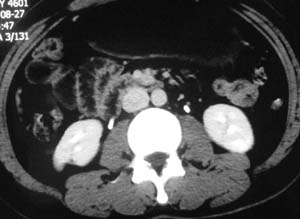

以下是引用子期在2010-3-19 20:47:00的发言:[br]血管畸形的ct增强应该有明显强化,本例并不相符合。本例双肾局部的略低密度影,累及肾盂,局部皮质明显变薄、内陷,增强扫描有轻度的强化,应考虑为炎性病变,患者为年轻男性,累及双肾的感染以结核较常见,可以没有明显的临床症状,尿中有时候也并不能查出什么;肾脓肿常有明显感染中毒症状,本例不符,另外一般的肾盂肾炎或肾小球肾炎通过小便就可确诊,其它还不能排除的是黄色肉芽肿性肾盂肾炎,然而单凭ct一般也很难鉴别。